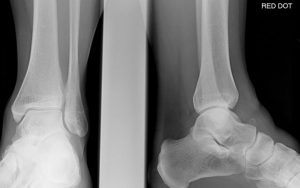

Перелом таранной кости

При разрыве слоевища пациент испытывает сильную боль и дискомфорт. Это серьезная травма, требующая правильного лечения и своевременной медицинской помощи. Высокая кость расположена между пяточной, большеберцовой и малоберцовой костями. Он небольшой по размеру, но выполняет важную функцию. К пластине не прикреплены мышцы. Анатомия таранной кости и локализация Талус редко получает травмы. Он несет на себе весь …